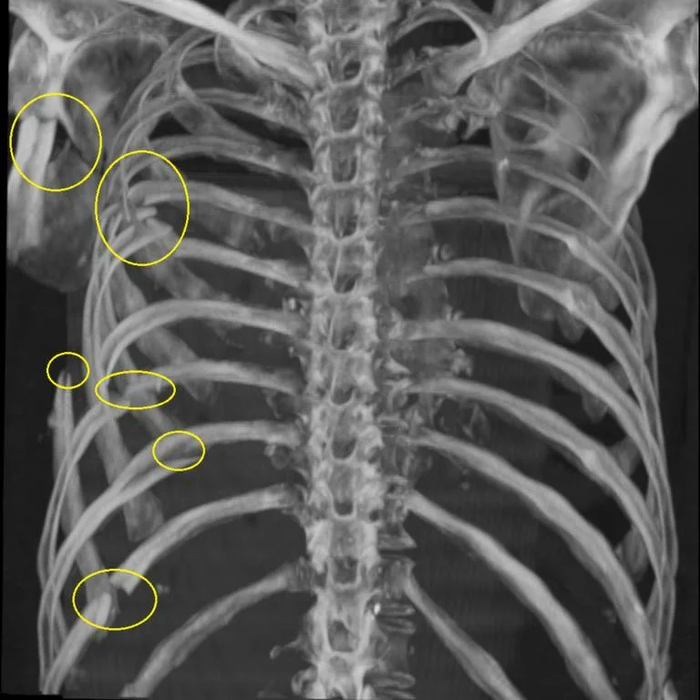

Для примера. Белая часть правого лёгкого "не просвечивается" из-за скопления крови в плевральной полости. Взято из открытых источников.

Оказалось, что у него было сломано 6 (шесть!) ребер с одной стороны и развился гемоторакс. Выжил. Более того, ещё он стал примером, который я привожу, когда какой-нибудь больной жалуется на боль от царапины, ушиба, растяжения и прочие мелкие травмы. Уважением к нему я проникся.

Для примера. Только тут сломанные ребра слева. Взято из открытых источников.